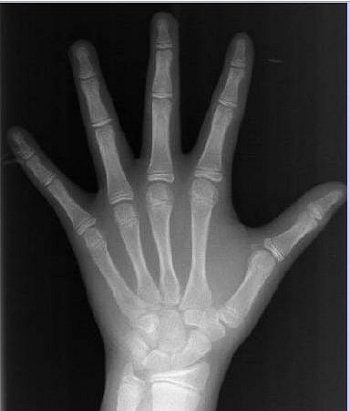

| Digital x-ray of an African-American girl of 10.14 years. |

The most important bone features for bone age assessment (BAA) were extracted. These were the length and width of the phalanges, number and overlap of the carpal bones, and stages of fusion of the epiphyses.

The bone age was assessed by two independent pediatric radiologists. Bone features were classified and stored in the digital hand atlas along with patient data such as height, weight, trunk height, and age.